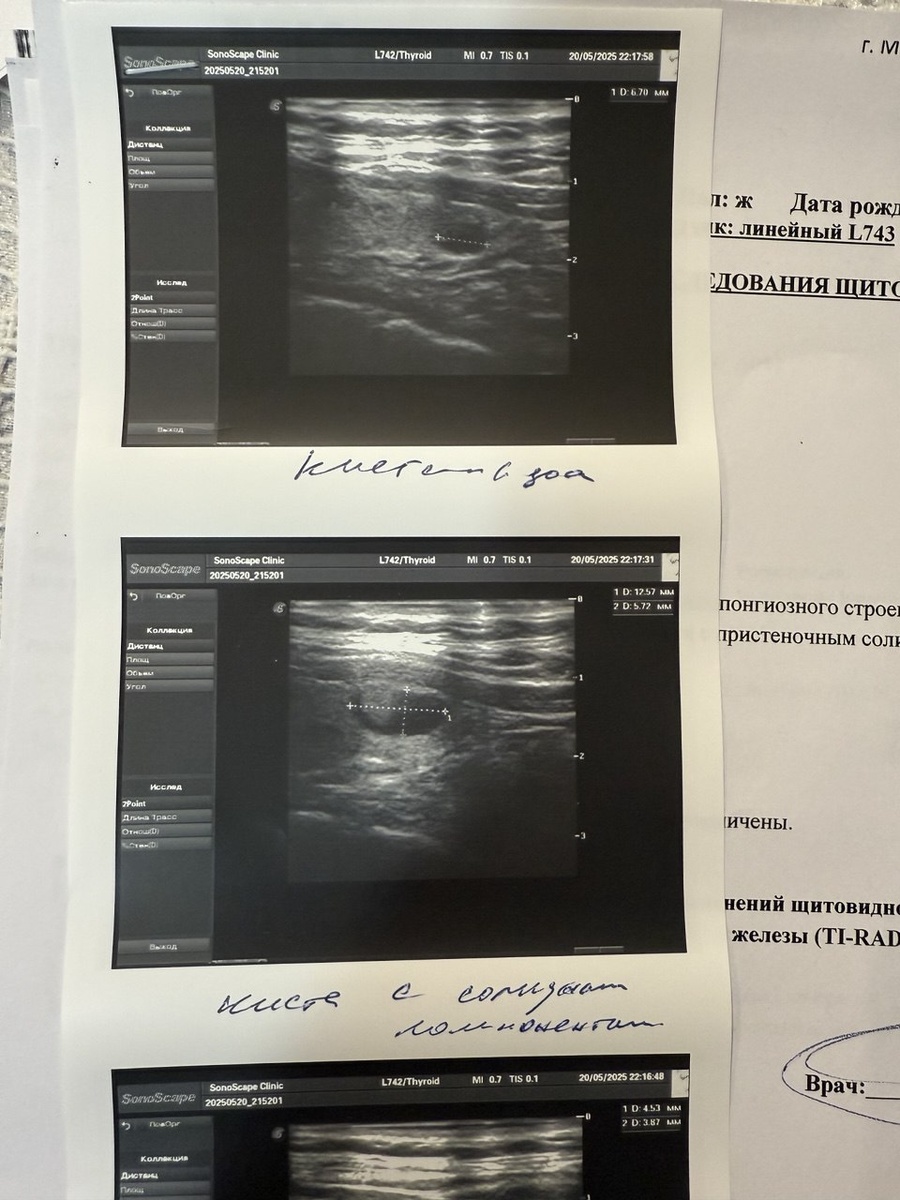

На втором приёме врач обратила внимание на образования в моей щитовидной железе и направила меня на ультразвуковое исследование. Пару дней назад я его сделала и до сих пор в недоумении... У меня и узлы, и кисты на щитовидной железе. Врач УЗИ сказал, вроде пока всё не страшно, но нужно наблюдать. Особенно за одной, самой большой кистой.

Все эти кистозные образования, которые есть у меня в щитовидной железе, вероятно, также могут препятствовать быстрому наступлению беременности. Так что буду разбираться дальше со своим здоровьем. Прием у эндокринолога будет на следующей неделе. Посмотрим, что она мне скажет. Врач УЗИ сказал, что в таких случаях могут предложить пункцию...